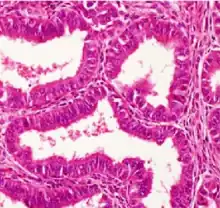

| Histopathology of a well-differentiated endometrioid adenocarcinoma in the ovary | |

Light microscopy shows tubular glands, resembling endometrium.[8]